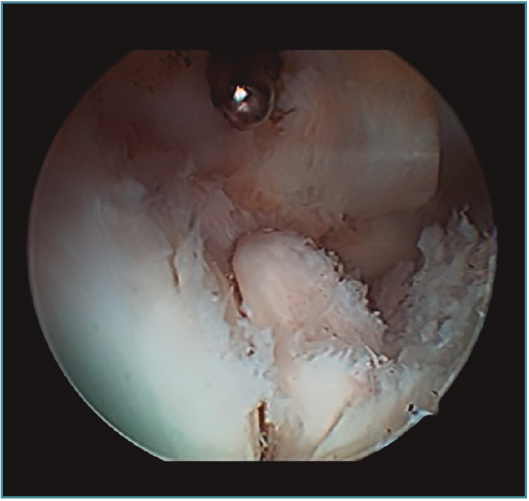

Acto seguido, realizamos nuestra secuencia de trabajo descrita anteriormente (visualización, creación de espacio, trabajo óseo y trabajo de partes blandas). El fresado óseo debe realizarse siempre con el instrumental motorizado orientado hacia el húmero, para evitar las lesiones de partes blandas. El uso de fresas o el sinoviotomo en modo no oscilante y a alta velocidad nos permitirá eliminar los osteofitos que interfieran con la movilidad, especialmente aquellos que ocupan la fosa radial o coronoidea (Figura 8). También es frecuente tener que eliminar osteofitos que aumentan la altura de la coronoides (Figura 9). Una vez eliminado el material óseo (Figura 10), flexionamos el codo para comprobar el aumento de flexión conseguido, que no será completo hasta que liberemos la cápsula posterior y la banda posterior del ligamento colateral medial. Como último paso en la cámara anterior, procedemos a la eliminación de la cápsula articular. Introducimos un Basket recto desde el portal anteromedial y vamos mordiendo la cápsula, atrapándola, cortándola y realizando un movimiento de batido hacia proximal para separar el fragmento capsular de las partes blandas anteriores. Progresamos lateralmente, descubriendo el vientre muscular del braquial anterior, hasta que aparezca tejido graso detrás de la cápsula resecada. En este momento, cambiamos los portales y miramos desde el portal anteromedial proximal y utilizamos la pinza Basket desde el portal anterolateral. Una vez realizada esta capsulotomía amplia, usamos el sinoviotomo para eliminar los restos capsulares proximales. Durante todo este proceso, utilizamos un retractor desde el portal anterolateral proximal para tensar la cápsula y proteger, sobre todo, el nervio radial, que queda situado justo en la grasa lateral al músculo braquial y anterior a la cabeza del radio, y a escasos milímetros de nuestro instrumental de trabajo; aunque no es aconsejable, es posible traccionar de él e introducirlo en la articulación con ayuda de un palpador introducido en la grasa que lo recubre. El nervio mediano se encuentra medial al músculo braquial, pero en un plano bastante más anterior, lo cual hace que esté mucho más protegido(12,13).

Figura 10. Mismo caso que en las Figuras 8 y 9 después del trabajo óseo. Obsérvese la recreación y fusión de ambas fosas radial y coronoidea con el típico aspecto de “tobogán” después del fresado de la cara anterior del húmero y la disminución de la altura de la coronoides. Todavía no se ha procedido a realizar la capsulectomía.